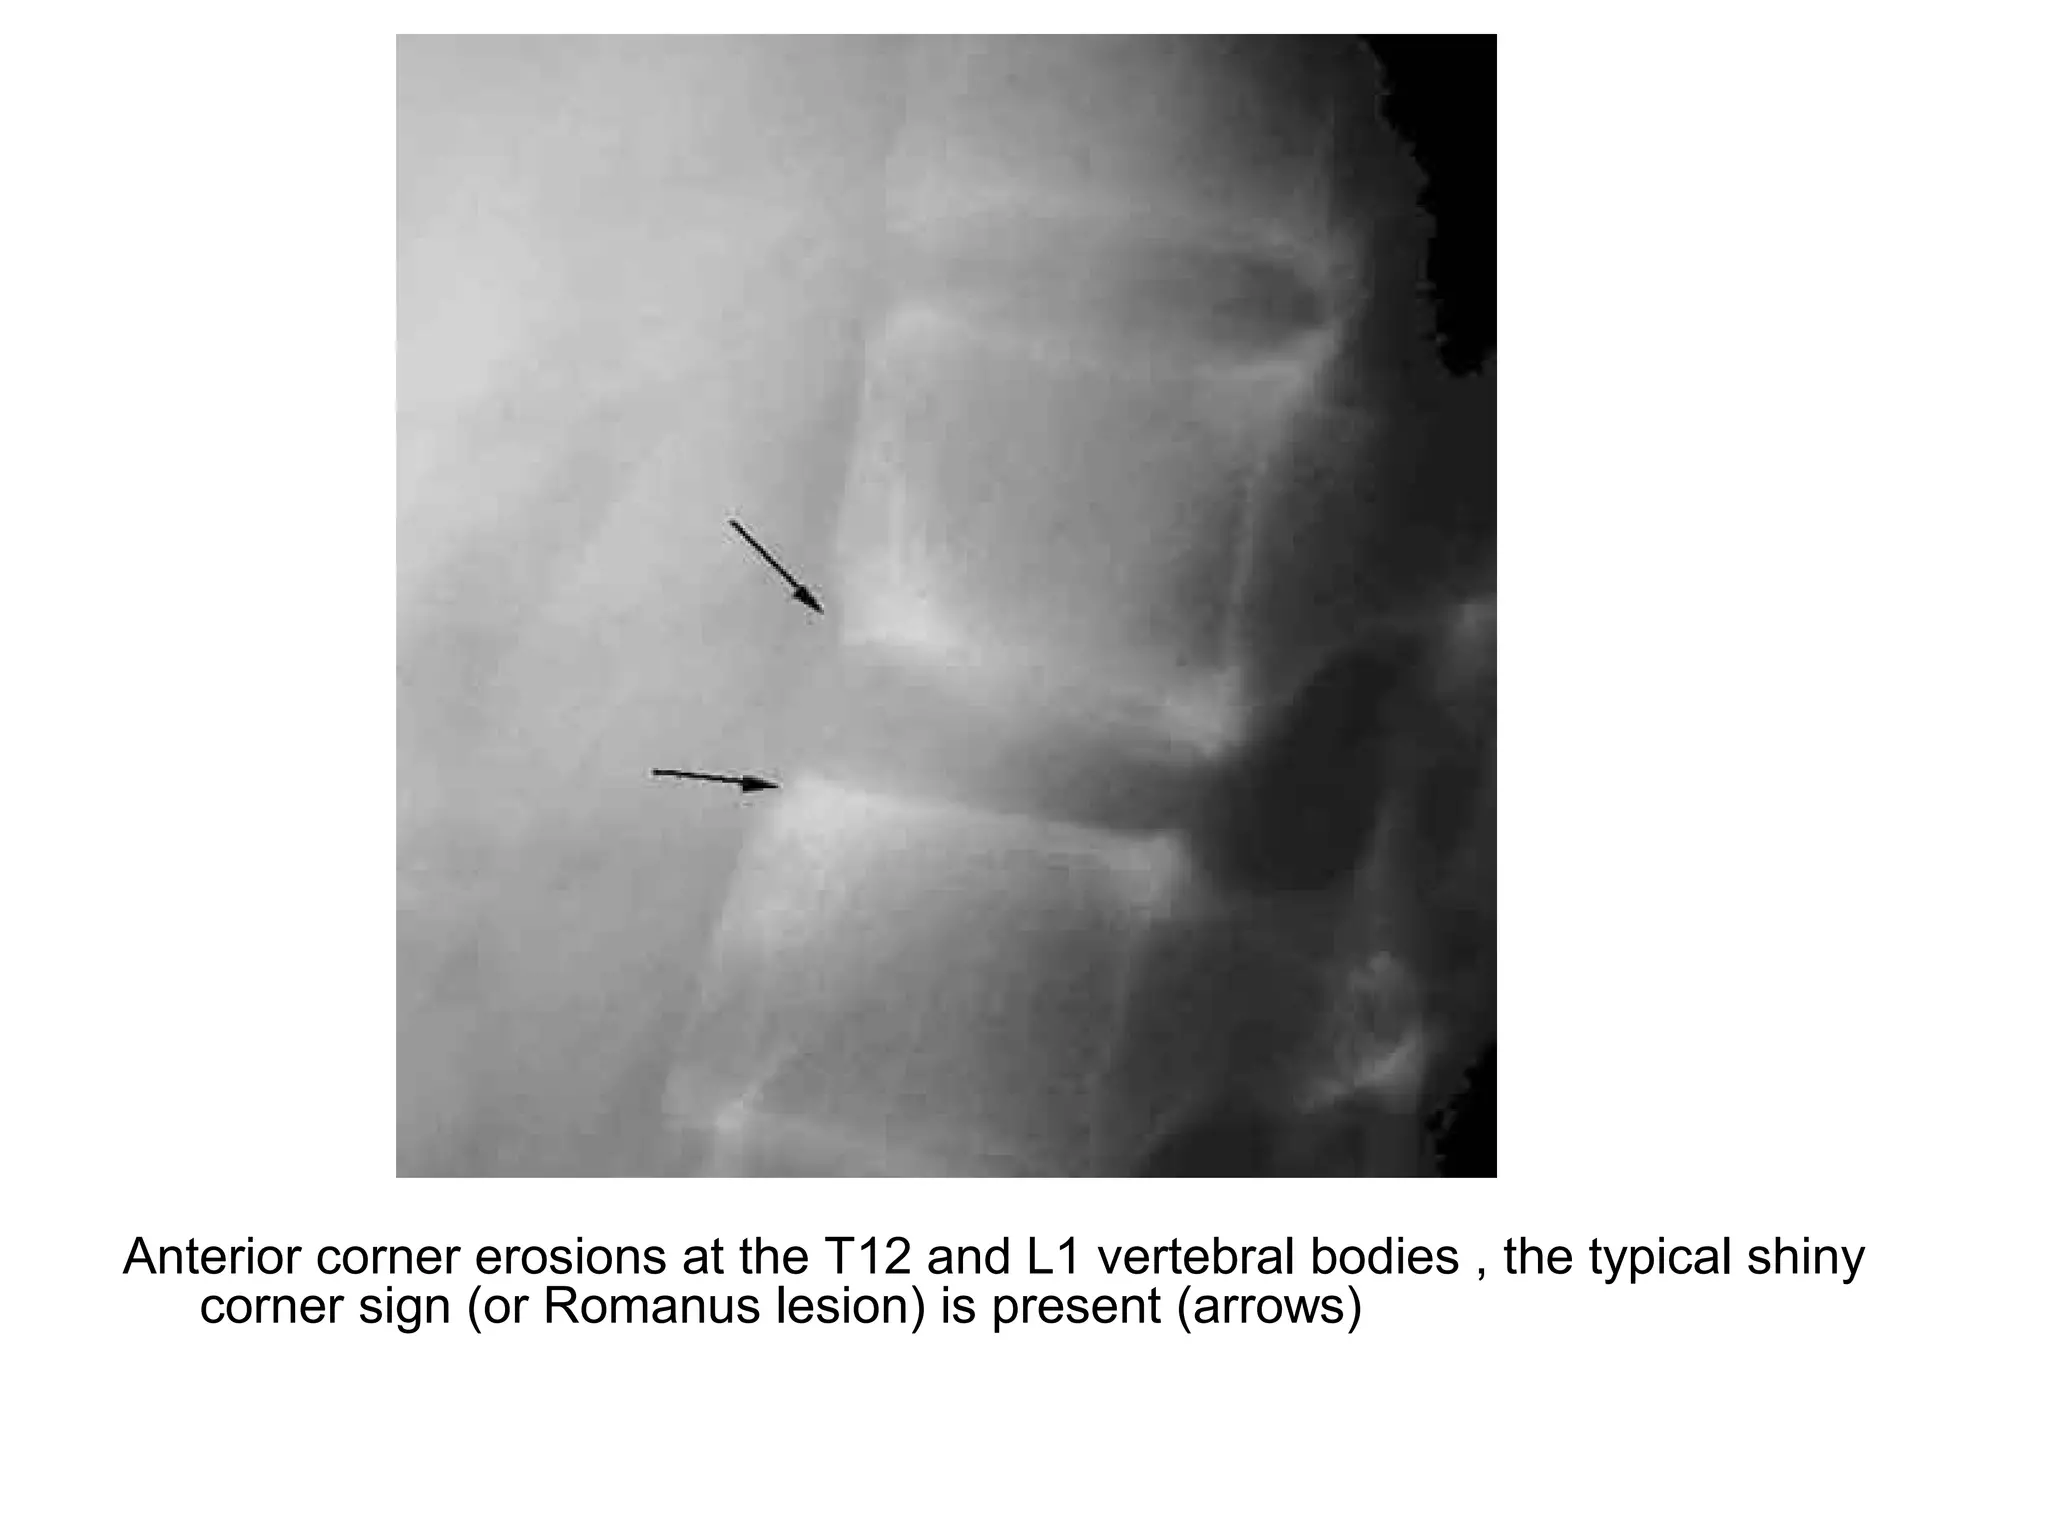

1-Shiny corner sign :

-Represents small erosions at the superior and

inferior endplates (corners on lateral radiograph)

of the vertebral bodies with surrounding reactive

sclerosis , Romanus lesions are erosions wjile

shiny corners are sclerosis of prior Romanus

lesions at the corner of the body

Romanus lesion (yellow arrow) , Shiny corner sign (red arrow)

Shiny corner sign

Anterior corner erosions at the T12 and L1 vertebral bodies , the typical shiny

corner sign (or Romanus lesion) is present (arrows)